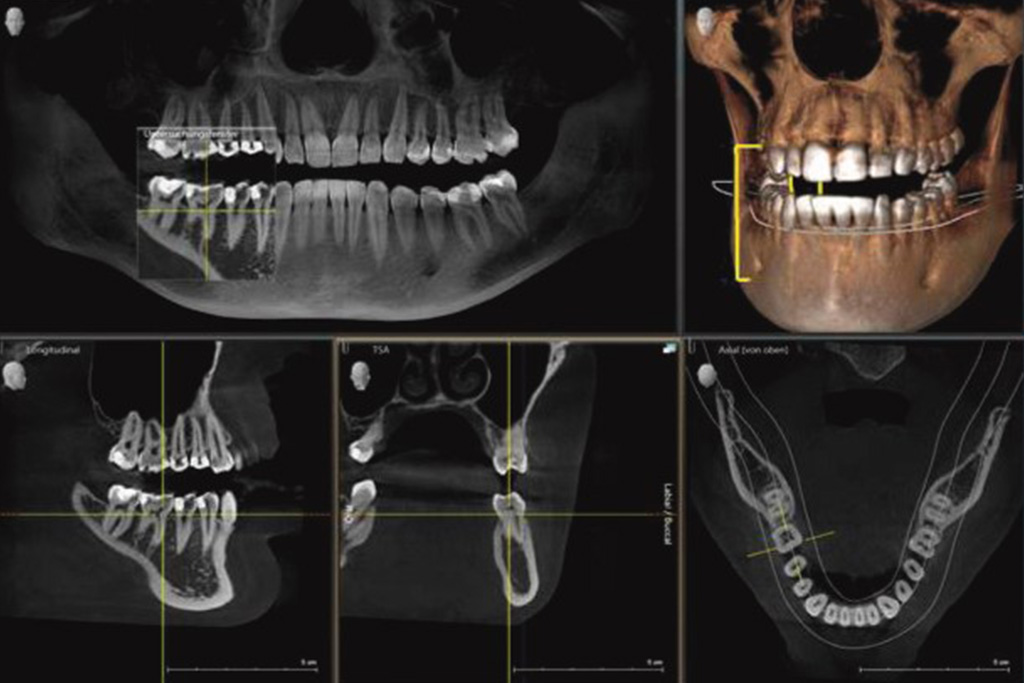

Beim digitalen 3D-Röntgen (DVT) werden von Ihrem Kiefer 3D-Röntgenbilder anfertigt, auf denen Ihre Kieferknochen, Ihre Zähne sowie das umliegende Gewebe, wie beispielsweise Nervenverlauf und Kieferhöhlen, genau dargestellt werden. So kann Ihr Zahnarzt alle Kieferstrukturen dreidimensional betrachten. Im Unterschied zur herkömmlichen 2D-Diagnostik entstehen beim 3D-Röntgenbild keine Überlagerungen, Verzerrungen oder Artefakte, sodass auch kleine Details eindeutig erkennbar sind.

Ihre Vorteile der 3D-Röntgentechnik: Das strahlungsarme 3D-Röntgenverfahren wird durch ein innovatives 3D-Röntgengerät (DVT) ermöglicht. Dieses erzeugt eine dreidimensionale Ansicht des Schädels und des Kiefers ohne jegliche Verzerrung. Das gestattet Ihrem Zahnarzt eine exakte Röntgenbefundung der Kieferstruktur, eine präzise Therapieplanung und somit beste Behandlungsergebnisse.